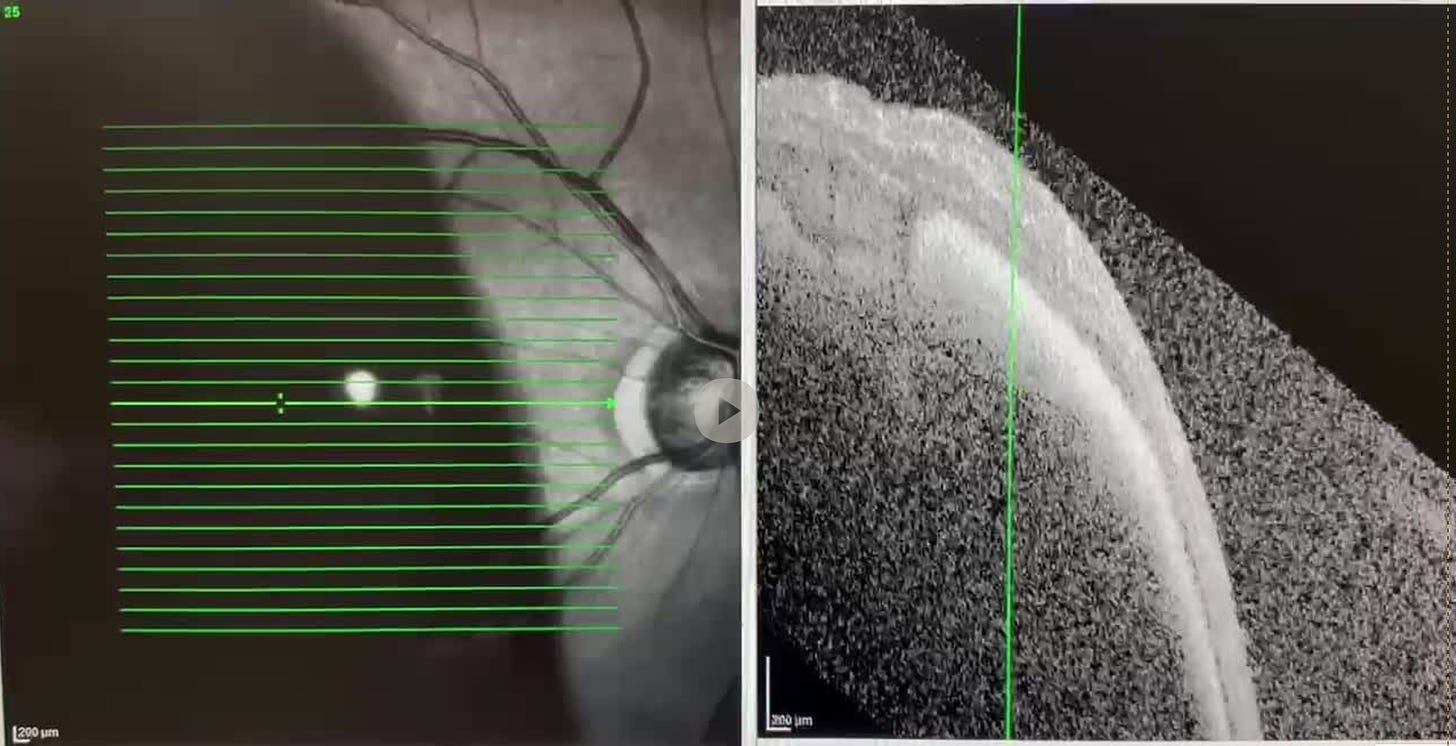

I have a lot of blood under my RPE… that is the problem

Steven Kirsch - Jul 27th 2024 8:07pm EDT OCT scan image of me I have a subretinal hemorrhage (SRH). This caused <500 microns of blood under my retina. This can be easily cleared through surgery (injecting TPA + gas bubble). The big problem is that there is a substantial amount of clotted blood under the very thin RPE layer. If this blood isn’t […]

I’m currently blind in one eye from a subretinal hemorrhage (SRH); with your help, it won’t be permanent

Steven Kirsch - Jul 26th 2024 9:41pm EDT

I have a subretinal hemorrhage (SRH). I was just sitting at the computer when it happened, analyzing the Czech Republic data. My eye looks like this: It was caused by either a central serous retinopathy (CSR) that burst (which started when I was under a lot of stress with all the work I was doing), […]VSRF LIVE: Episode 136 – Pfizer Whistleblowers

While working on the Czech Republic data I went blind in my right eye